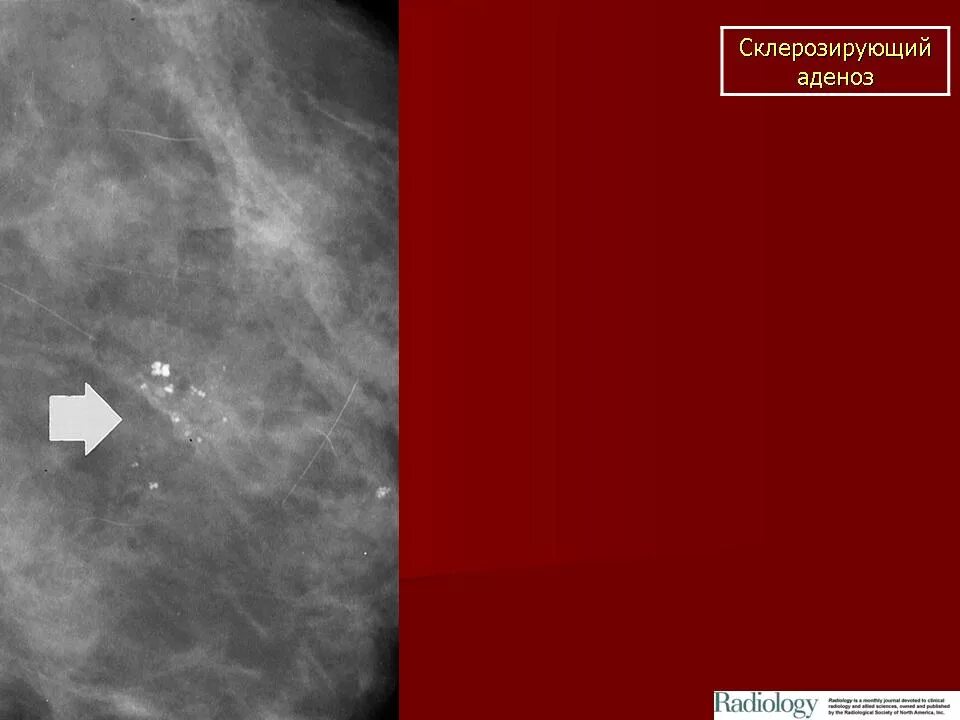

Склерозирующий аденоз молочных желез